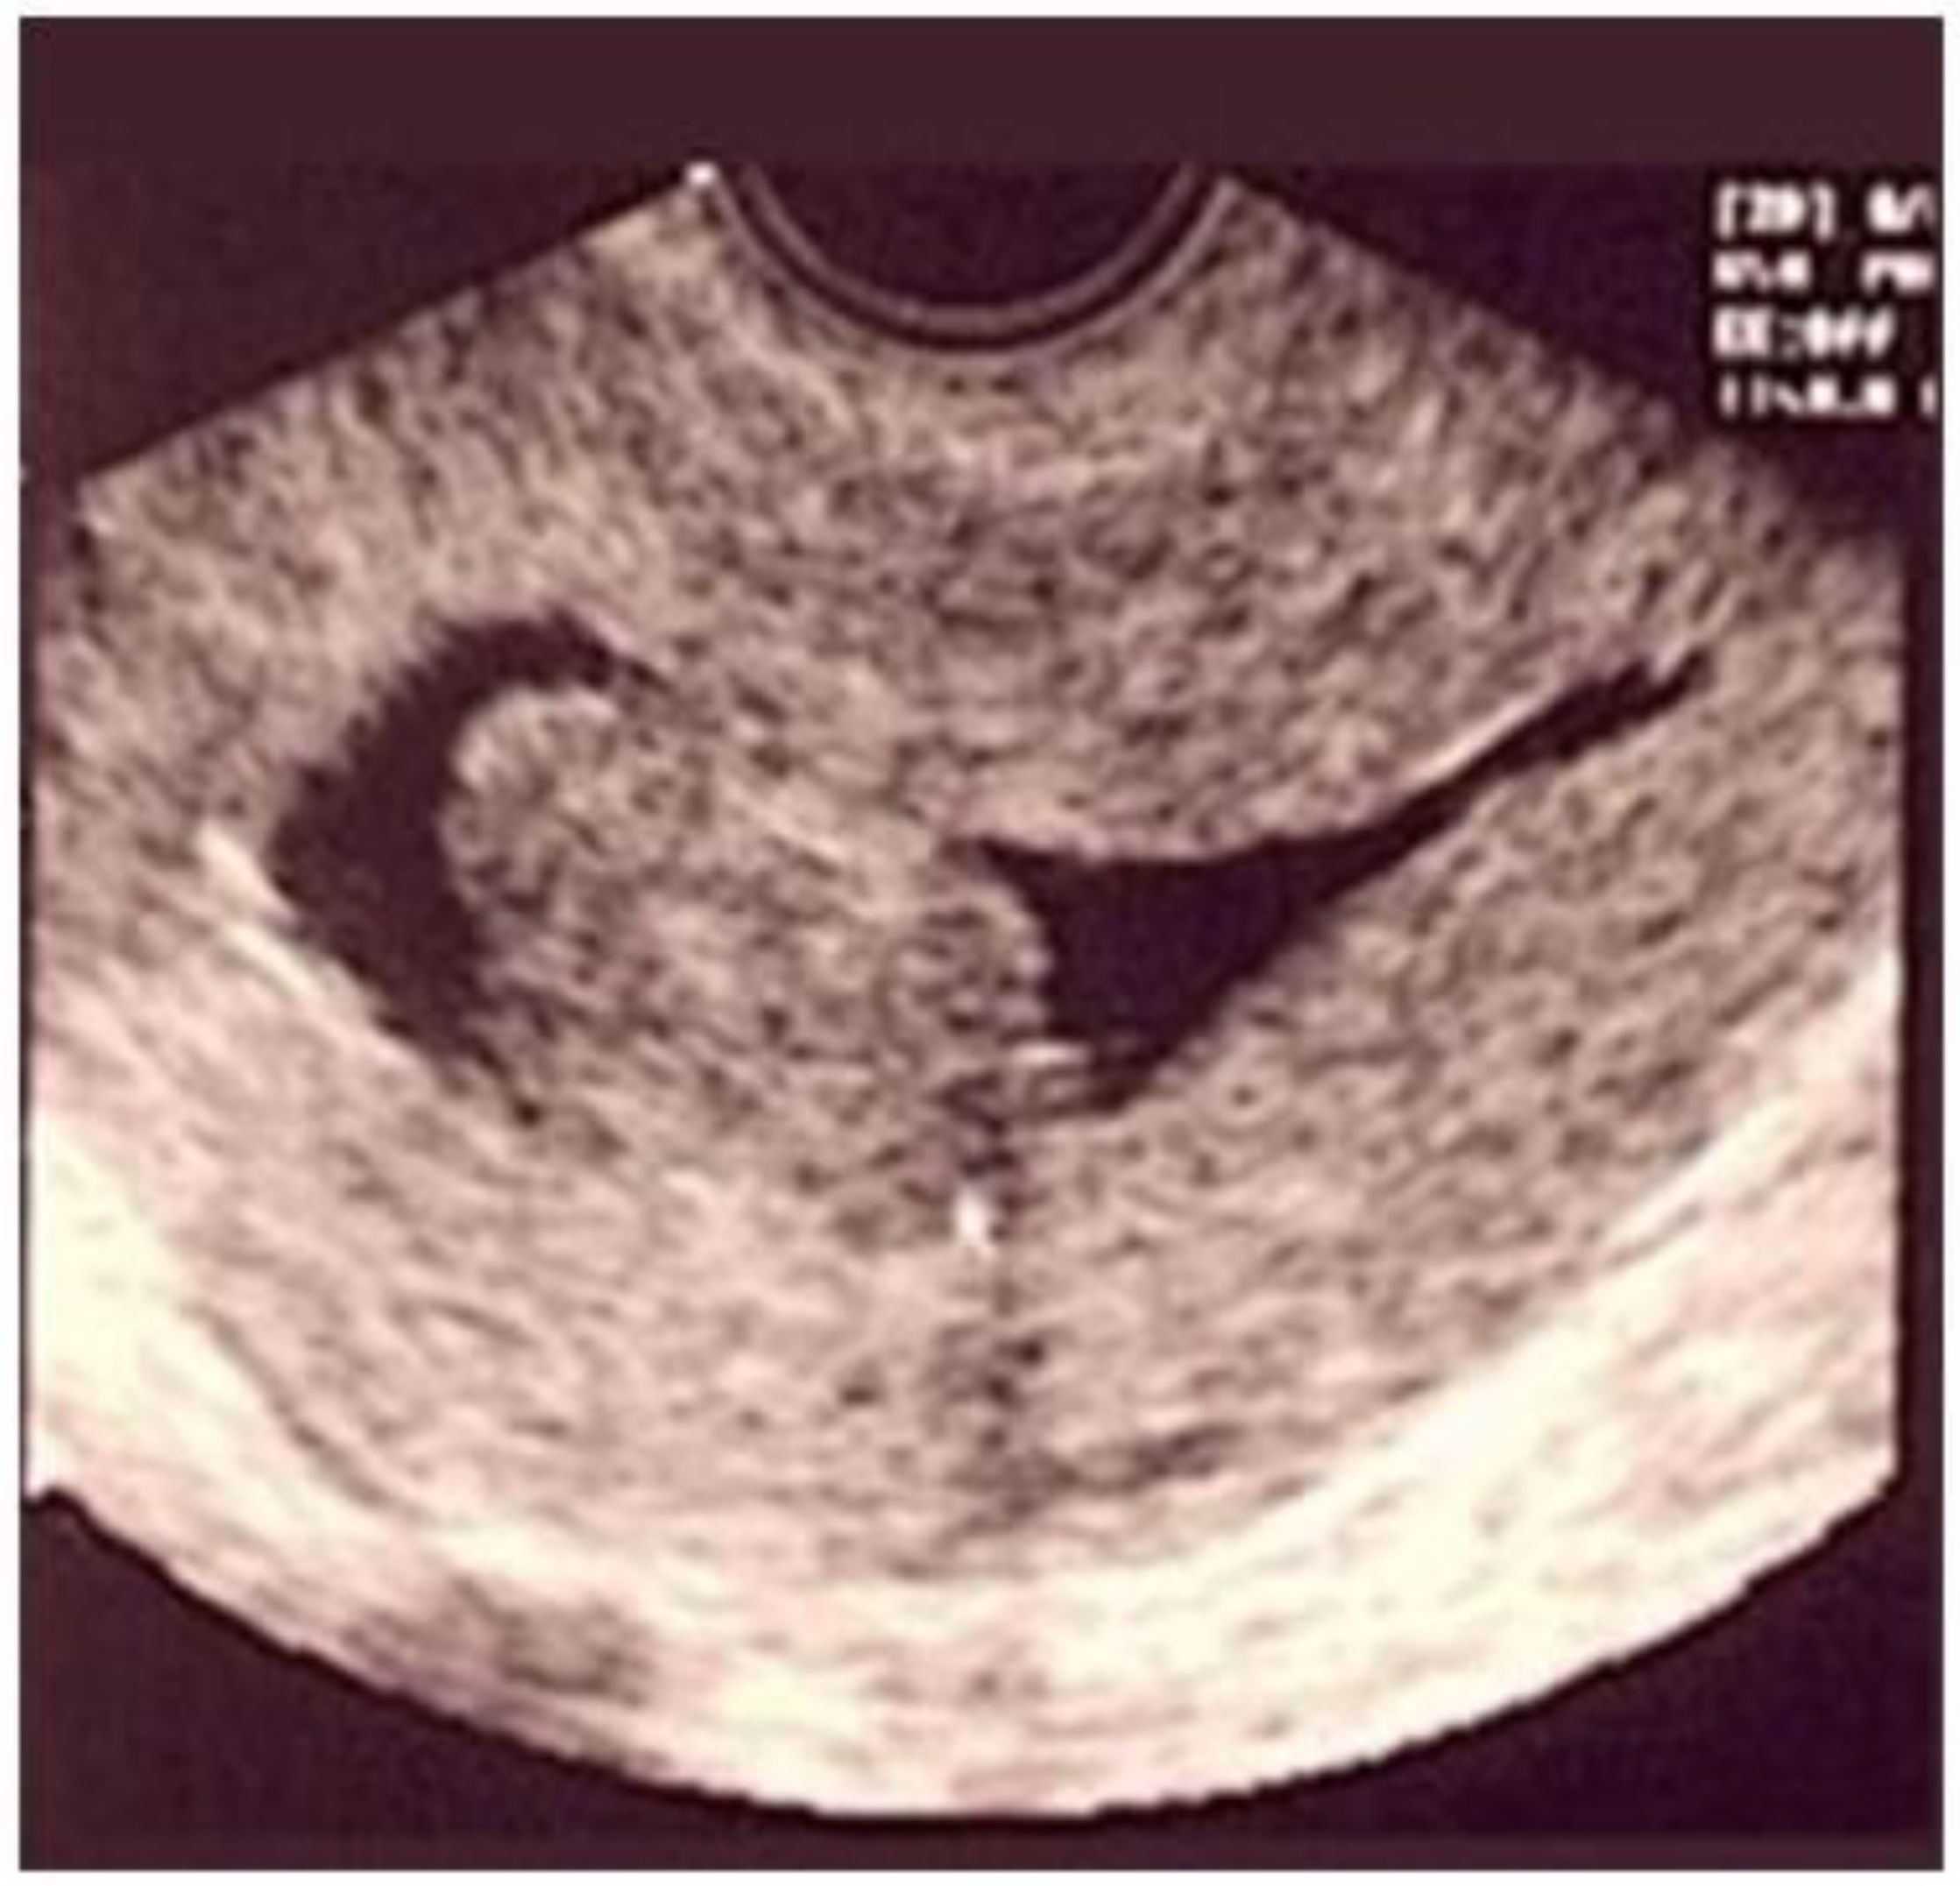

Ultrasonography (USG), especially transvaginal ultrasound (TVUS), is the routine exam and is usually the first one performed; it has good accuracy, easy access, and low cost, but it has a limited role in the presence of a large uterus or multiple nodules, as posterior acoustic shadowing makes it difficult to evaluate and count them. It is important in the evaluation of the intramural component of the myoma and the free myometrial mantle up to the serosa, but it is operator-dependent (Figure 2).

Figure 2. Submucous myoma on ultrasound. * Submucosal fibroid.